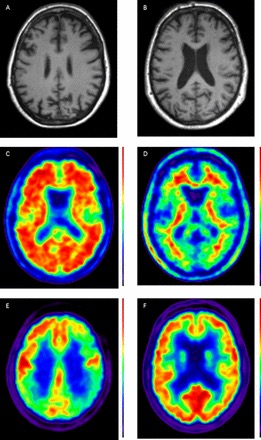

In practice, combining several of these different biomarkers, each of which provides different insights into the underlying disease process, may increase diagnostic certainty (see Case Study figure 1).

Figure 1

Case showing clinical use of biomarkers. A 56 year old patient presented with a 5–10-year history of ‘scattiness’. Three years ago she developed difficulties reading an analogue clock, her spelling had declined and she had difficulty reading, losing her place from line to line. She received a clinical diagnosis of posterior cortical atrophy. Subsequently episodic memory became impaired. At the time of scanning, the Mini-Mental State Examination score was 19/30. A T1 volumetric MRI of the brain demonstrated a posterior pattern of cortical atrophy (A) with preserved hippocampal volumes compared with a healthy control patient (B); A 18F-florbetpair amyloid positron emission tomography (PET) scans shows widespread cortical amyloid deposition (C) compared with a healthy control (D) fludeoxyglucose (18F) PET scan demonstrates a posterior dominant pattern of hypometabolism (E) SUVR 1.0–1.4, compared with an age matched healthy control (F) SUVR 1.0–1.5. Cerebrospinal fluid examination demonstrated an elevated t-tau: 1080 pg/mL (NR 146–595); Aβ1–42 360 pg/mL ((NR 627–1322) giving a tau/Aβ1–42 ratio of 3. This case illustrates how different biomarkers can provide complementary information including regional neuronal loss, more widespread metabolic dysfunction, as well as confirming the underlying pathology—in this case, Alzheimer's disease. (NB for clinical purposes, 18F-florbetapir images should be interpreted on a grey rather than colour scale.)